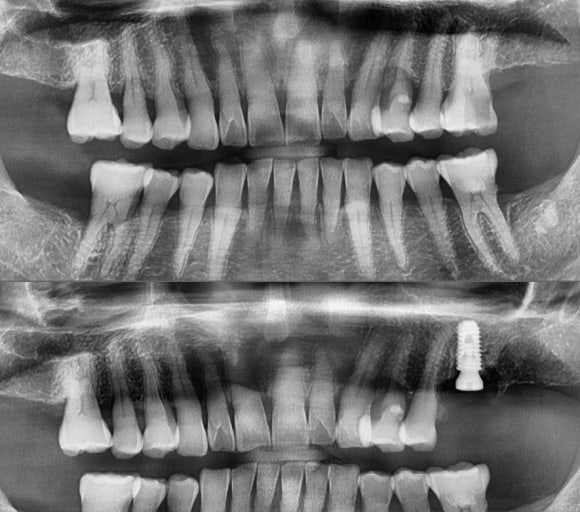

발치 후 즉시 임플란트를 식립함.

만 65세 이상이시기 때문에 보험 임플란트로 하셨음.

발치를 해보니 아니나 다를까 palatal 뿌리에 금이 가 있었음.

발치 시, 뼈가 다치지 않기 위해 매우 조심해서 발치를 했음.

뼈가 다치면 임플란트를 6개월 뒤에 식립해야 하므로...

고생했지만 별다른 뼈의 외상없이 발치를 완료하고 당일에 식립할 수 있었음.